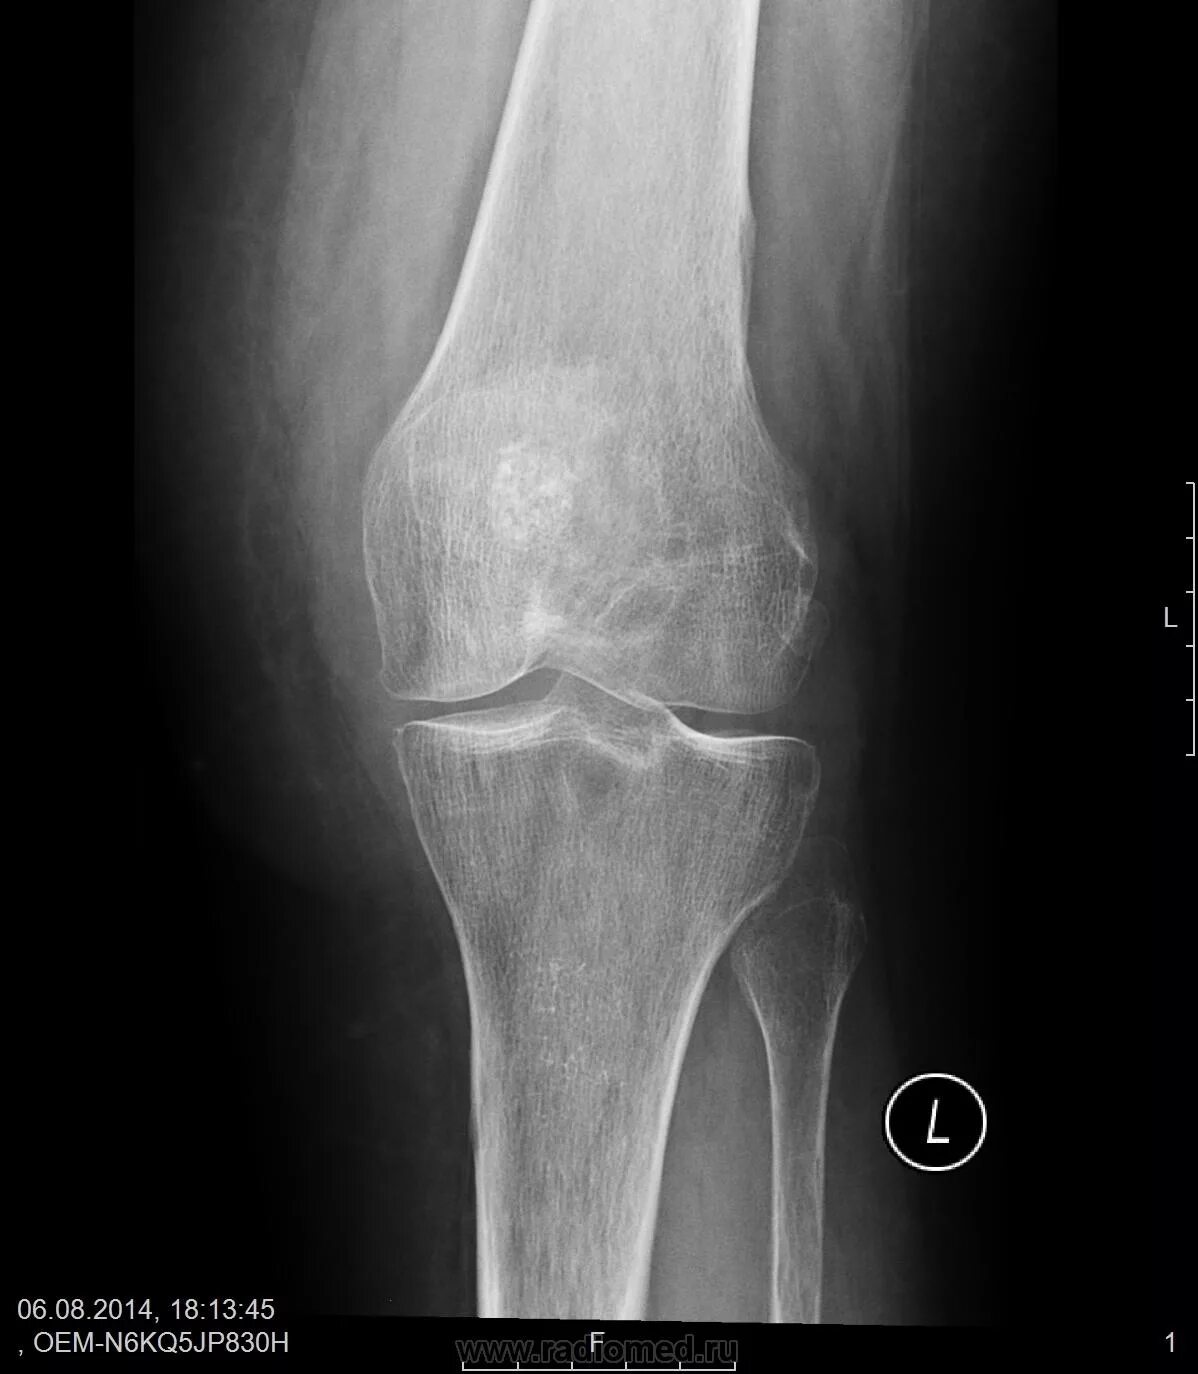

Гонартроз мрт